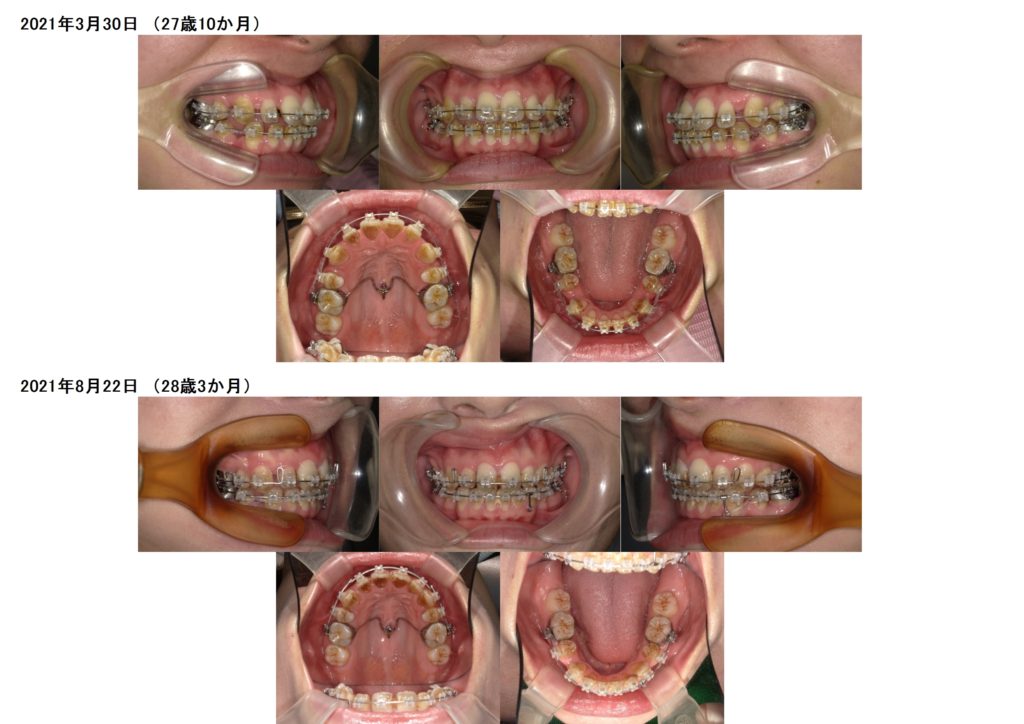

使用する必要がある方にはアンカースクリューのお話を診断時にさせていただいておりますが、1本の方、2本の方口腔内の状況によって異なります。

中には途中から左右に埋め込む方もいらっしゃるので治療例、治療経過によっても異なるので、その時はご説明させていただきますね。

徐々に抜歯した隙間、特に上顎の隙間がぐんぐんと閉じていっているのが分かりますよね